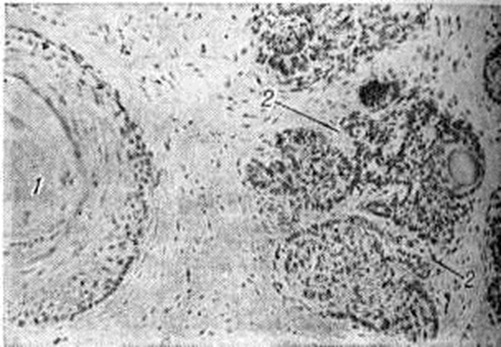

Микропрепарат трихоэпителиомы кожи (кистозная форма): 1 — кистозная полость, содержащая роговые массы; 2 — базалиомоподобные разрастания; окраска гематоксилин-эозином; ×160.

Макроскопически Трихоэпителиома имеет вид маленького, диаметром до 1 сантиметров, плотноватого чётко очерченного узла бледно-розового или желтоватого цвета, иногда с мелкими кистозными полостями на разрезе. Микроскопическое строение Трихоэпителиома весьма разнообразно. Характерная пилоидная (в направлении фолликулов волос) дифференцировка может быть выражена в различной степени: от едва намечающихся концентрических плоскоэпителиальных структур с ороговением в центре до почти зрелых фолликулов волос с наличием уродливых волосяных стержней. В зависимости от преобладания соответствующих структур выделяют кистозный, светлоклеточный, солидный и смешанный морфологический варианты Трихоэпителиома Это разделение не имеет клинические, значения, но важно для морфологический дифференциальной диагностики. Наиболее часто встречается кистозная Трихоэпителиома, содержащая кистозные со своеобразной плоскоэпителиальной выстилкой полости, заполненные бледно-окрашивающимися роговыми массами (смотри рисунок).

Стенки кистозных полостей имеют неравномерную толщину, встречаются участки клеток плоского эпителия с очаговой кератинизацией и элементами незрелых волосяных стержней. Часто наблюдаются отходящие от плоскоэпителиальных комплексов базалиомоподобные тяжистые разрастания. Иногда вокруг опухолевых комплексов обнаруживаются полосы, подобные гиалиновым мембранам, окружающим фолликулы волос в норме. Может иметь место частичное разрушение опухоли за счёт гигантоклеточной реакции и обызвествления.